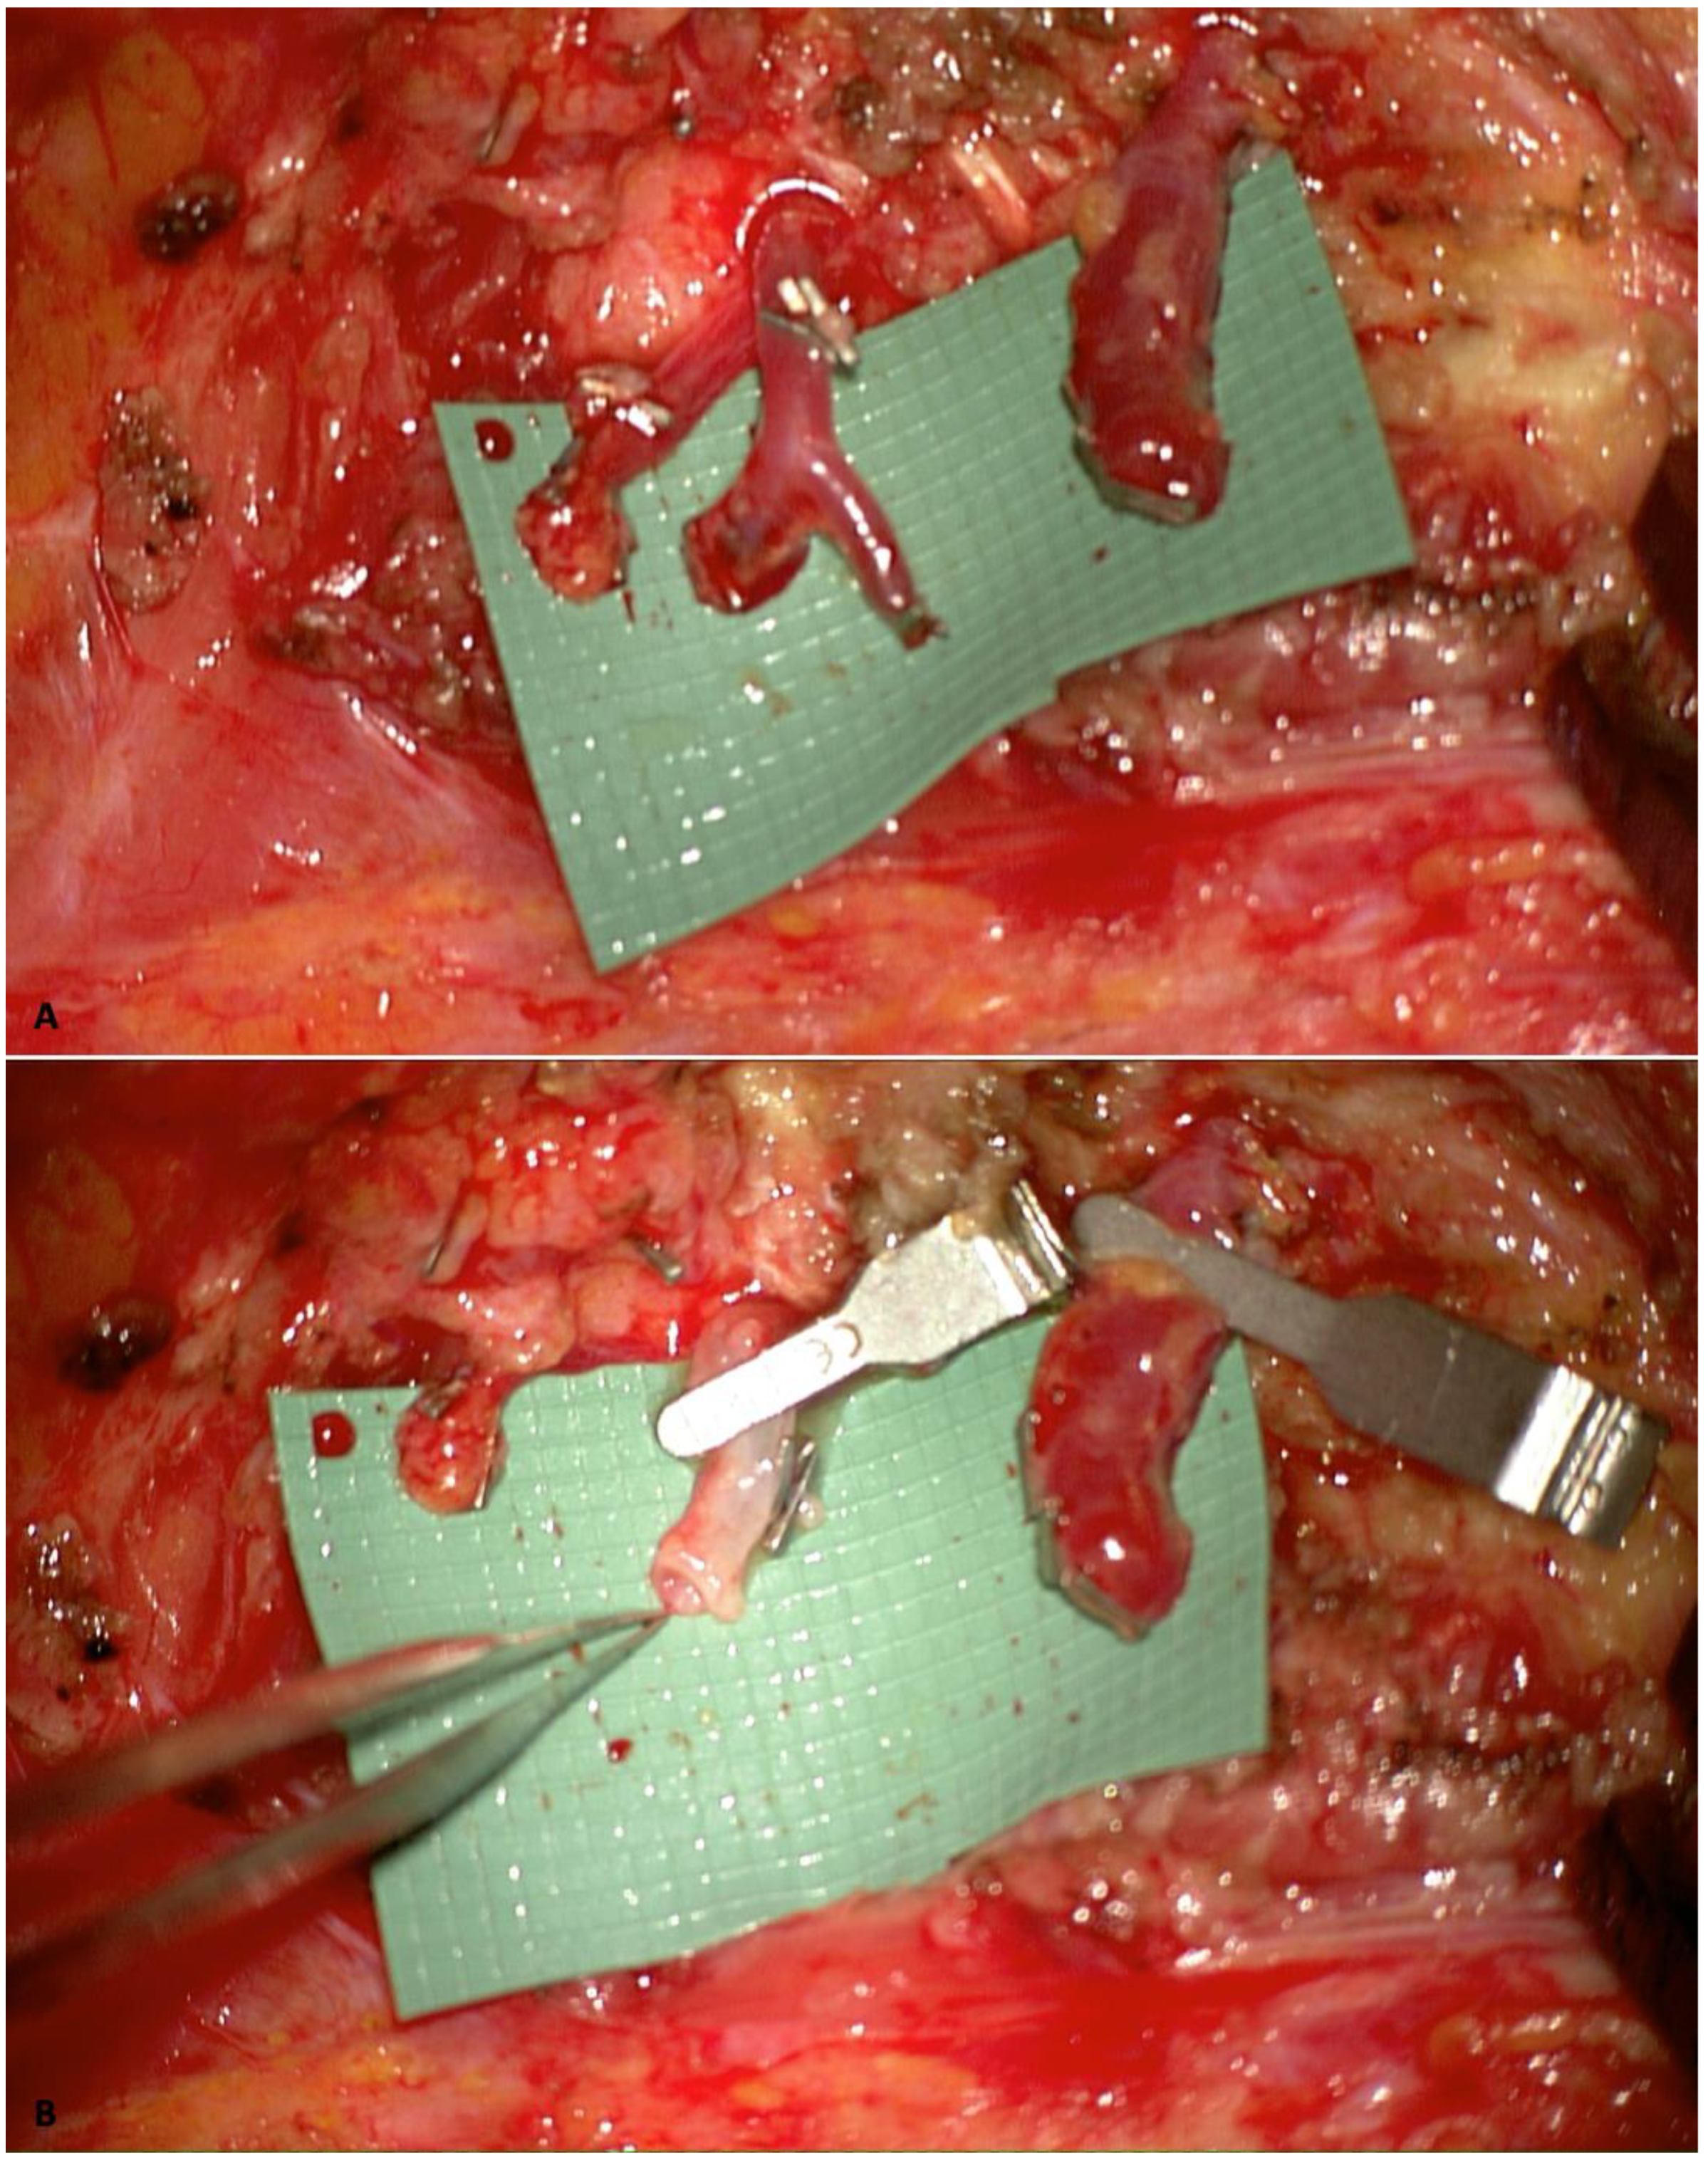

2.2. Internal Mammary Artery Perforator-to-Perforator Anastomosis and Rib-Sparing Approach

- Hamdi, M.; Blondeel, P.; Van Landuyt, K.; Monstrey, S. Algorithm in choosing recipient vessels for perforator free flap in breast reconstruction: The role of the internal mammary perforators. Br. J. Plast. Surg. 2004, 57, 258–265. [Google Scholar] [CrossRef] [PubMed]

- Vourvachis, M.; Goodarzi, M.R.; Scaglioni, M.F.; Tartanus, J.; Jones, A.; Cheng, H.; Abdelrahman, M. Utilization of the internal mammary perforators as the recipient vessels for microsurgical breast reconstruction: A systematic review and meta-analysis of the literature. Microsurgery 2023, 44, 31105. [Google Scholar] [CrossRef]

- Nocini, R.; Pinto, V.; Contu, L.; De Santis, G.; Pignatti, M. “Solving vessel caliber mismatch in microvascular anasto-mosis: A comprehensive review, novel techniques, and a surgical guide for optimal outcomes”. J. Hand Micro-Surg. 2024, 17, 100179. [Google Scholar] [CrossRef]